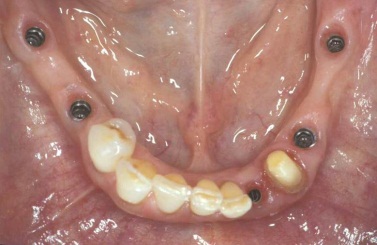

Bezzubá čelist

Bezzubá čelist je hlavní indikací pro ošetření pomocí implantátů. Zejména celkové zubní náhrady v dolní čelisti mají velice nízkou stabilitu a držení díky velkému úbytku kosti.

S pomocí zubních implantátů můžeme díky různým kotevním systémům (třmeny, kulové hlavy, Locatory) zajistit stabilitu a držení protézy nebo při použití většího počtu implantátů zhotovit pevné náhrady – můstky nalepené nebo našroubované na pevno na implantáty.

S těmito typy náhrad můžeme dosáhnout perfektní funkci, výbornou estetiku, fonetiku a současně zajistit u pacienta možnost dobré hygienickou péče a čištění, která je pro životnost implantátů velice důležitá.